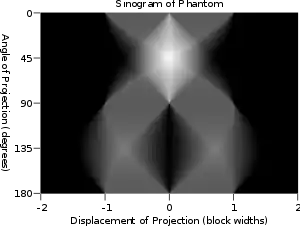

The Radon transform data is often called a sinogram because the Radon transform of an off-center point source is a sinusoid. Consequently, the Radon transform of a number of small objects appears graphically as a number of blurred sine waves with different amplitudes and phases.

Thus in an image processing context the original image can be recovered from the 'sinogram' data by applying a ramp filter (in the variable) and then back-projecting. As the filtering step can be performed efficiently (for example using digital signal processing techniques) and the back projection step is simply an accumulation of values in the pixels of the image, this results in a highly efficient, and hence widely used, algorithm. Explicitly, the inversion formula obtained by the latter method is:[4]